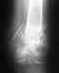

Никакого мумия и кальция в лечении перелома костей голени применять не нужно. С местным остеопорозом делать ничего не нужно. Нужно ли сейчас что-то делать с фиксатором (динамизировать ли, в частности), можно сказать после знакомства со рентгенограммой, отражающей сегодняшнюю ситуацию, а не апрельскую.